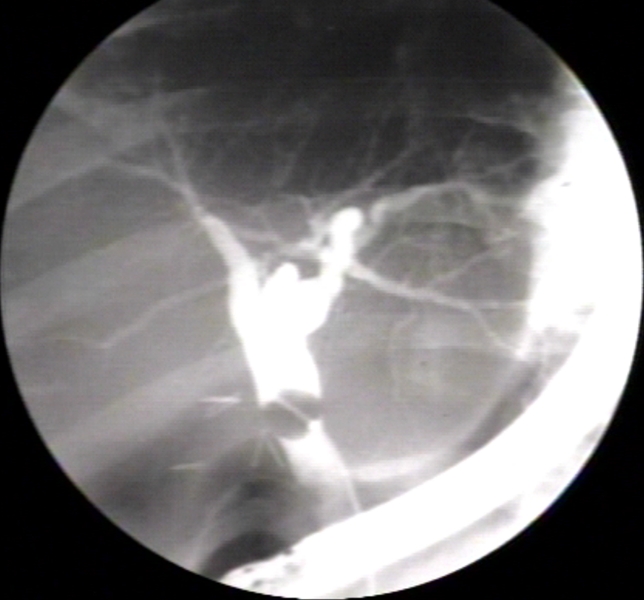

RADIOLOGY: HEPATOBILIARY: GALLBLADDER: CHOLECYSTECTOMY DURING PROCEDURE; SPHINCTEROTOMY, BALLOON IS VISIBLE IN MID PART OF BILE DUCT (PLAIN FILM)